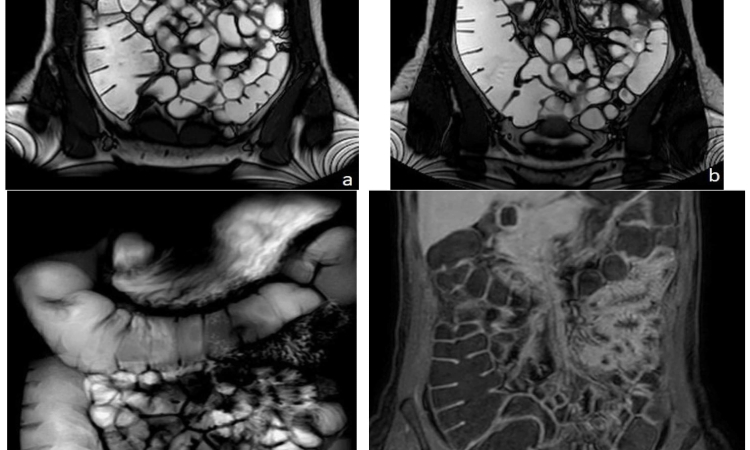

МРТ внутренних органов

Изучение состояния внутренних органов проводится сегодня с применением новейших методов, что позволяет достичь требуемого уровня точности. Записаться на МРТ внутренних органов в Бирюлево может любой желающий при появлении болезненных симптомов или по направлению от врача. Томография поможет выявить причины развития заболеваний и разработать программу лечения. Это ведущий метод диагностирования и контроля органов до и после операции.